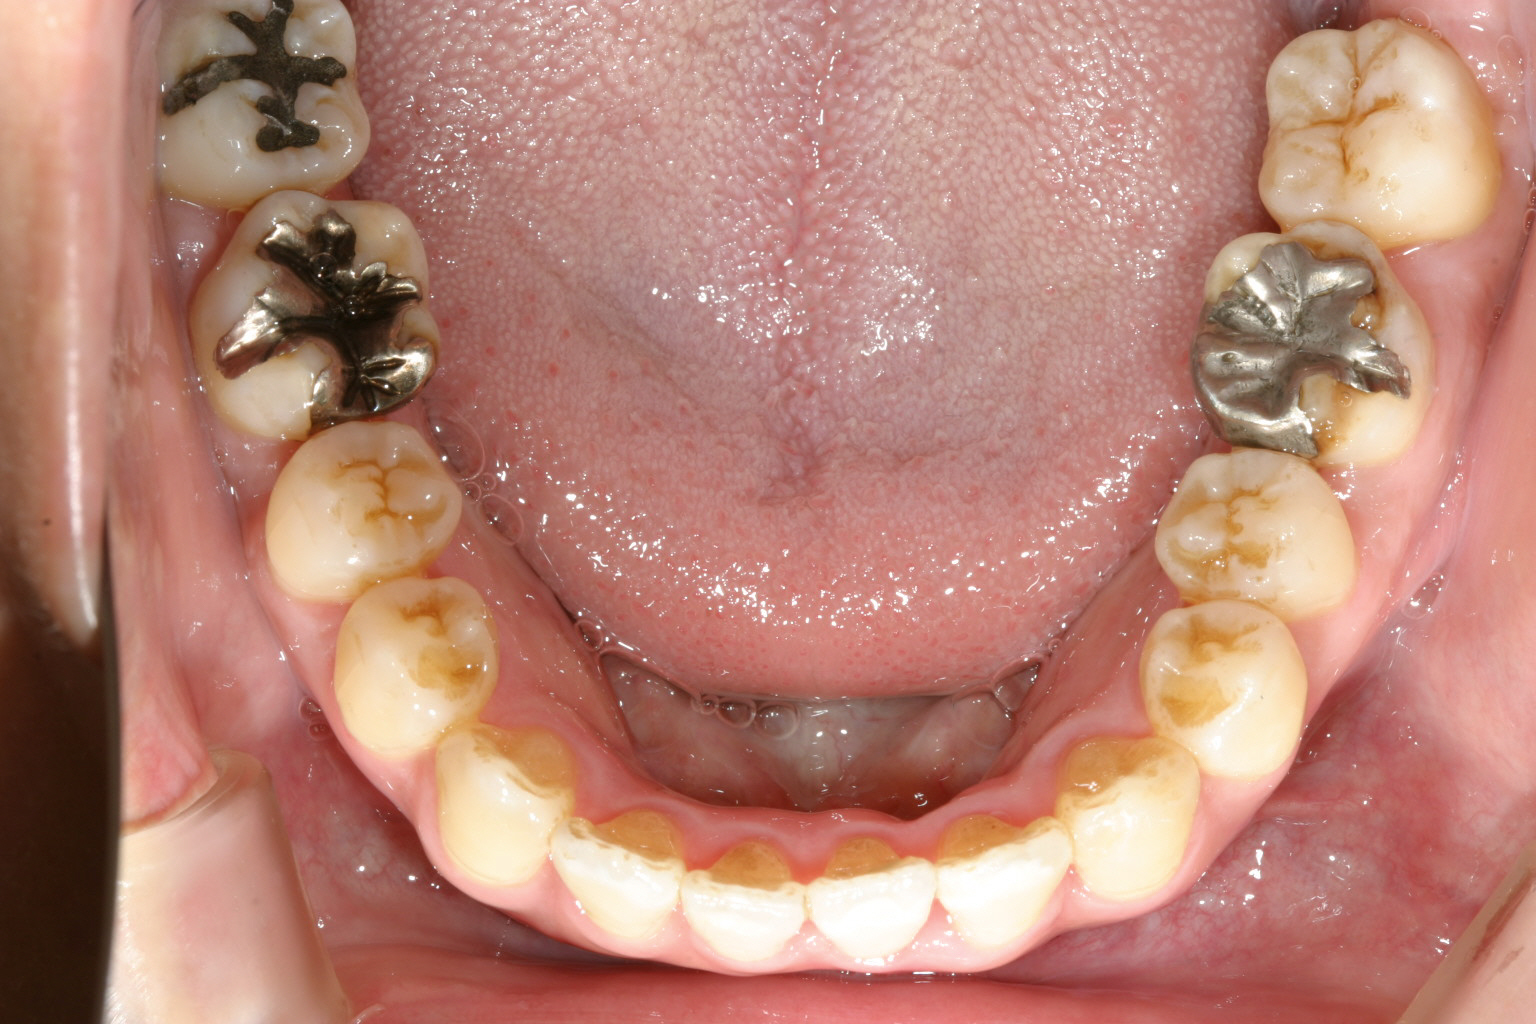

下顎の綺麗なU字になりました。

側面観も抜群です。

今回のケースは下顎の前歯の90度回転を戻すのに難儀しました。

何度かブラケットを貼り替えてリンガルにボタンをつけゴムの力で回転を助け

やっとの事で綺麗なアーチに仕上げました。

開咬閉じるより下顎前歯を整列させる方が難しかったです。

この様な開咬ケースにはやはりマルチループワイヤーに限ります。

毎回の調整に少し手間と時間がかかりますが確実に綺麗になります。